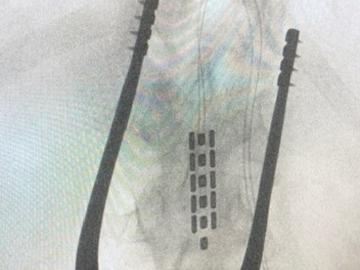

Clinical tools used in the lab include vascular and cardiac ultrasound, beat-by-beat blood pressure, cardiac, cerebral and spinal cord MRI, orthostatic stress testing, exercise stress testing, functional electrical stimulation, passive cycling, arterial blood gas reactivity testing (RespirAct Gen IV), both surgically implanted and non-invasive neurostimulation modalities, eye tracking, muscle sympathetic nervous system recordings, etc. Preclinical tools include various tissue clearing methods (CLARITY, uDISCO) arterial cannulation, nerve recordings, spinal cord transection/contusion, and a variety of genetic strains for manipulation (e.g., Th-Cre, PV-Cre). The lab is also employing a novel computational pipeline for managing large data-sets of physiological metrics.